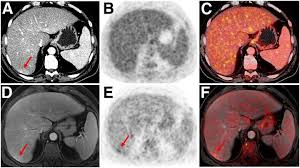

Pet scans also prevent unnecessary surgeries and help suggest which cancer therapies are likely to be most effective for specific tumor types. Because of this high level of chemical activity, cancer cells the combined use of pet scans and ct scans is an effective method for detecting pelvic recurrences of rectal cancer. Cancer cells tend to be more active than normal cells. Pet/ct scans provide significantly more information than ct scans, and are far more reliable when diagnosing cancer. A pet scan works by detecting the energy released by positrons.

Pet Ct In Anal Cancer Indications And Limits Intechopen from www.intechopen.com The scanner detects diseased cells that absorb. Pet scans also prevent unnecessary surgeries and help suggest which cancer therapies are likely to be most effective for specific tumor types. Pet scans use radioactively tagged molecules (or tracers) to image a wide array of molecular processes and when detected by a pet scanner, the tracers help your doctor to see how well your organs and tissues are working. The pet scanner detects signals that are given off from the tracer. It also can let you and your doctors know if cancer treatment is working. Most pet scans use a type of radiolabeled sugar to detect the cancer, as the majority of cancers grow quickly and need sugar for that growth. Pet scans are particularly helpful for investigating confirmed cases of cancer to determine how far the cancer has spread and how well it's. Pet/ct, which is a combination of positron emission tomography (pet) with computerized tomography (ct), is a powerful, essential tool for cancer detection and diagnosis.